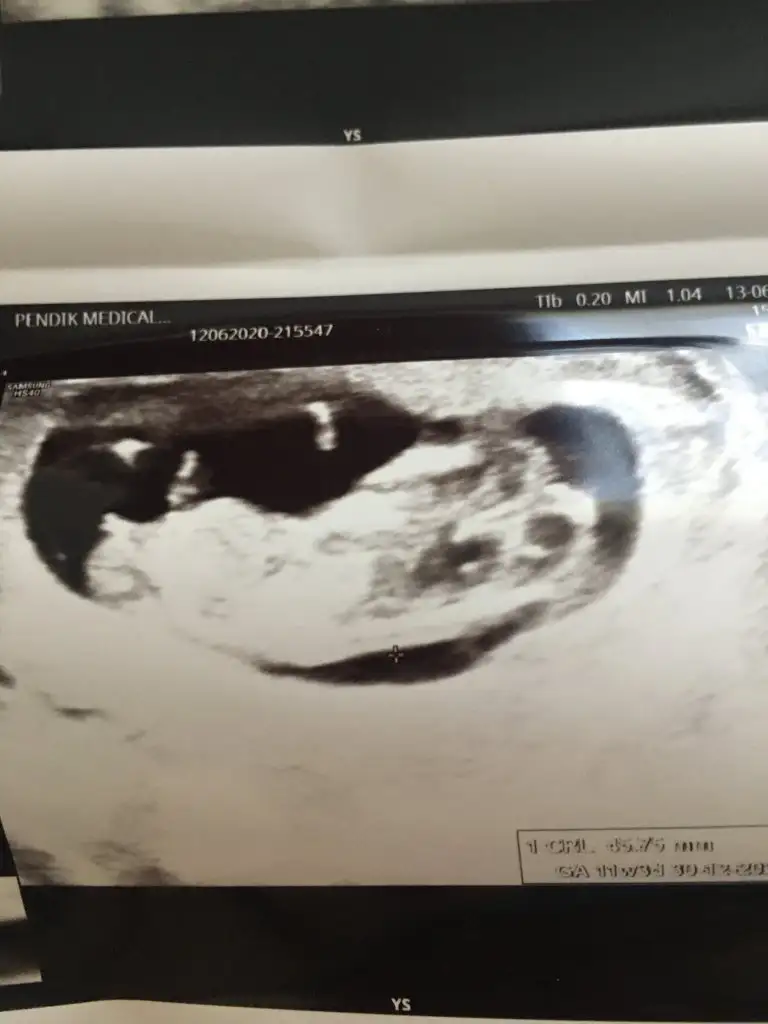

Kızlarr selam bende cinsiyet tahmini alabilir miyim😍

Eklentiler

• 91B2775E-DAD5-468E-9AA1-CF97C6A6E882.webp